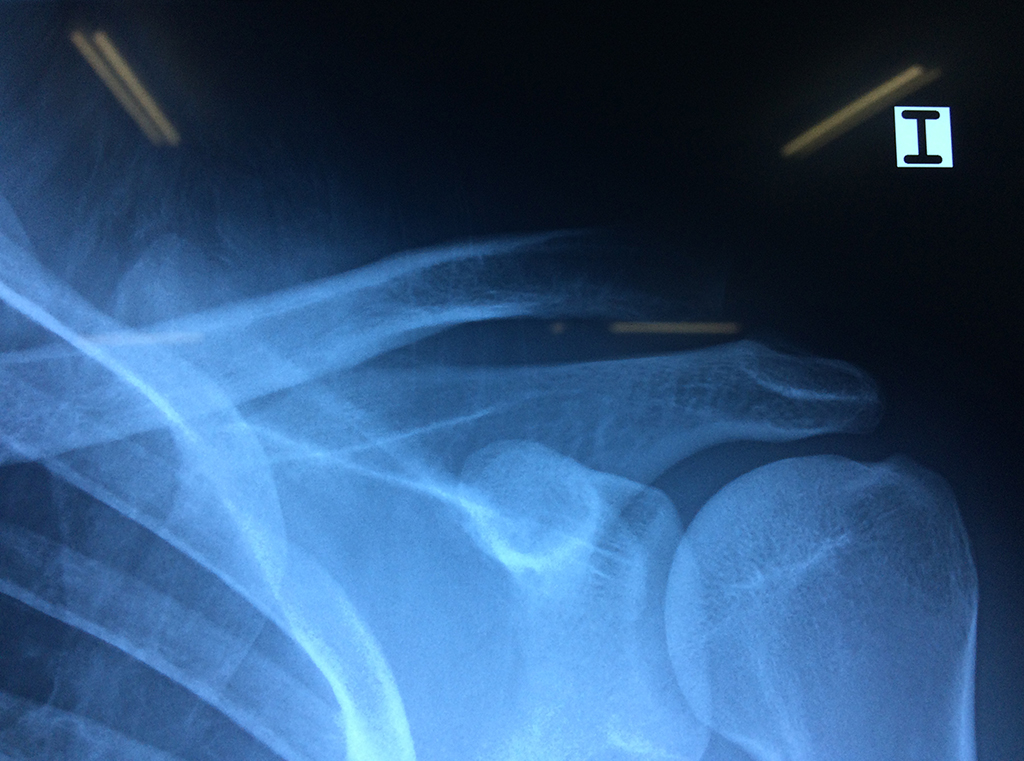

Exteriormente una envoltura de tejido blando circunda el conjunto, es la llamada cápsula articular que está reforzada por varios ligamentos que le dan estabilidad e impiden que los huesos se desplacen más allá de sus límites fisiológicos. Un conjunto de músculos y sus tendones se unen a las superficies de los huesos y hacen posible la movilidad de la articulación, entre ellos es muy importante el manguito rotador formado por cuatro músculos que proporcionan movilidad y estabilidad al hombro.

Varias estructuras transparentes en forma de saco llamadas bolsas serosas, permiten el deslizamiento suave de los diferentes componentes móviles. El hombro es la articulación con mayor amplitud de movimientos del cuerpo humano.